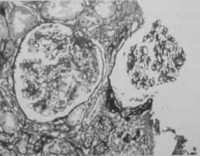

1.血管通透性增加 由于肺部的感染,中毒或血管栓塞时,病原体及其他谢产物可对微血管产生直接损害或通过血管活性物质的作用使微血管壁通秀性增加,红细胞自扩张的微血管内皮细胞间隙进入肺泡而造小量咯血。

2.血管壁侵蚀,破裂 肺部慢性感染使血管壁弹性纤维受损,局部形成小动脉血管瘤在剧烈咳嗽或动作时血管瘤破裂而大量出血,常造成窒息,突然死亡此种血管瘤多见于空洞性肺结核。

3.肺血管内压力增高 风湿性心脏疸同瓣狭窄,肺动脉高压,高血坟心脏病等情况下肺血管内压力增高,可造成血液外渗或小血管破裂而引起咯血。